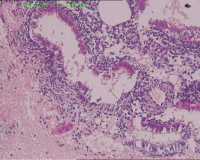

宫血

性别

女

年龄

40

临床诊断

一般病史

不规则流血1月

标本名称

宫内物

大体所见

灰褐碎组织一堆。

经期及增生早期子宫内膜。

增生期子宫内膜